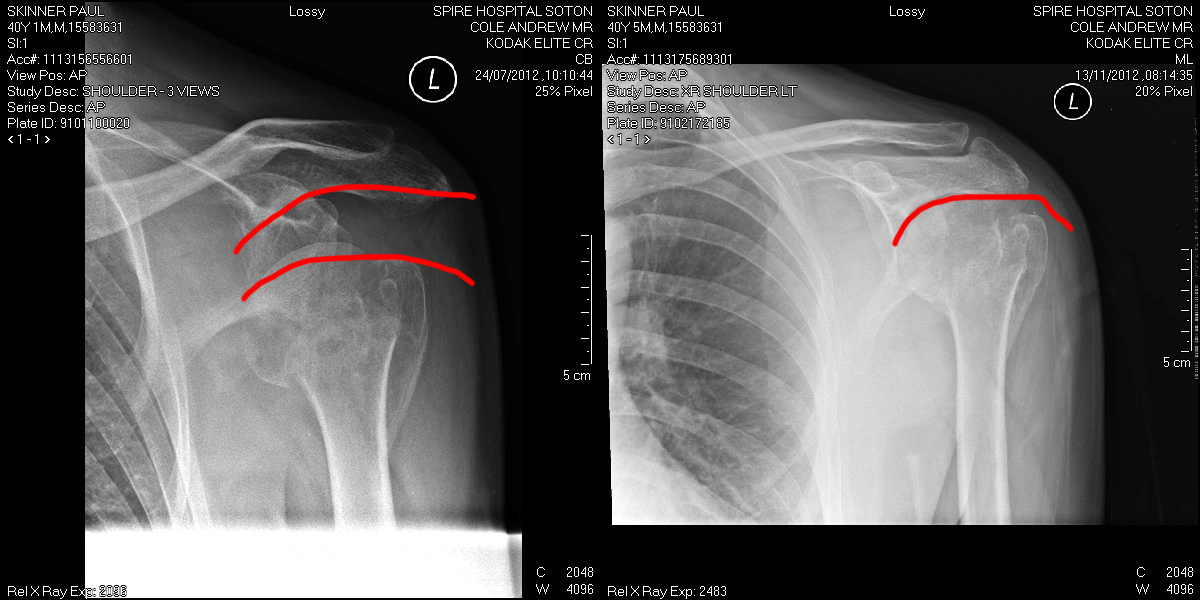

Which takes us on a neat arch to the purpose of this story. Last year we had a troubling situation in the business when our long-term programmer Paul Skinner had a huge reaction to a medical condition and his shoulder ended up orientated in a way that even the less-physiologically competent among us realised was all wrong.